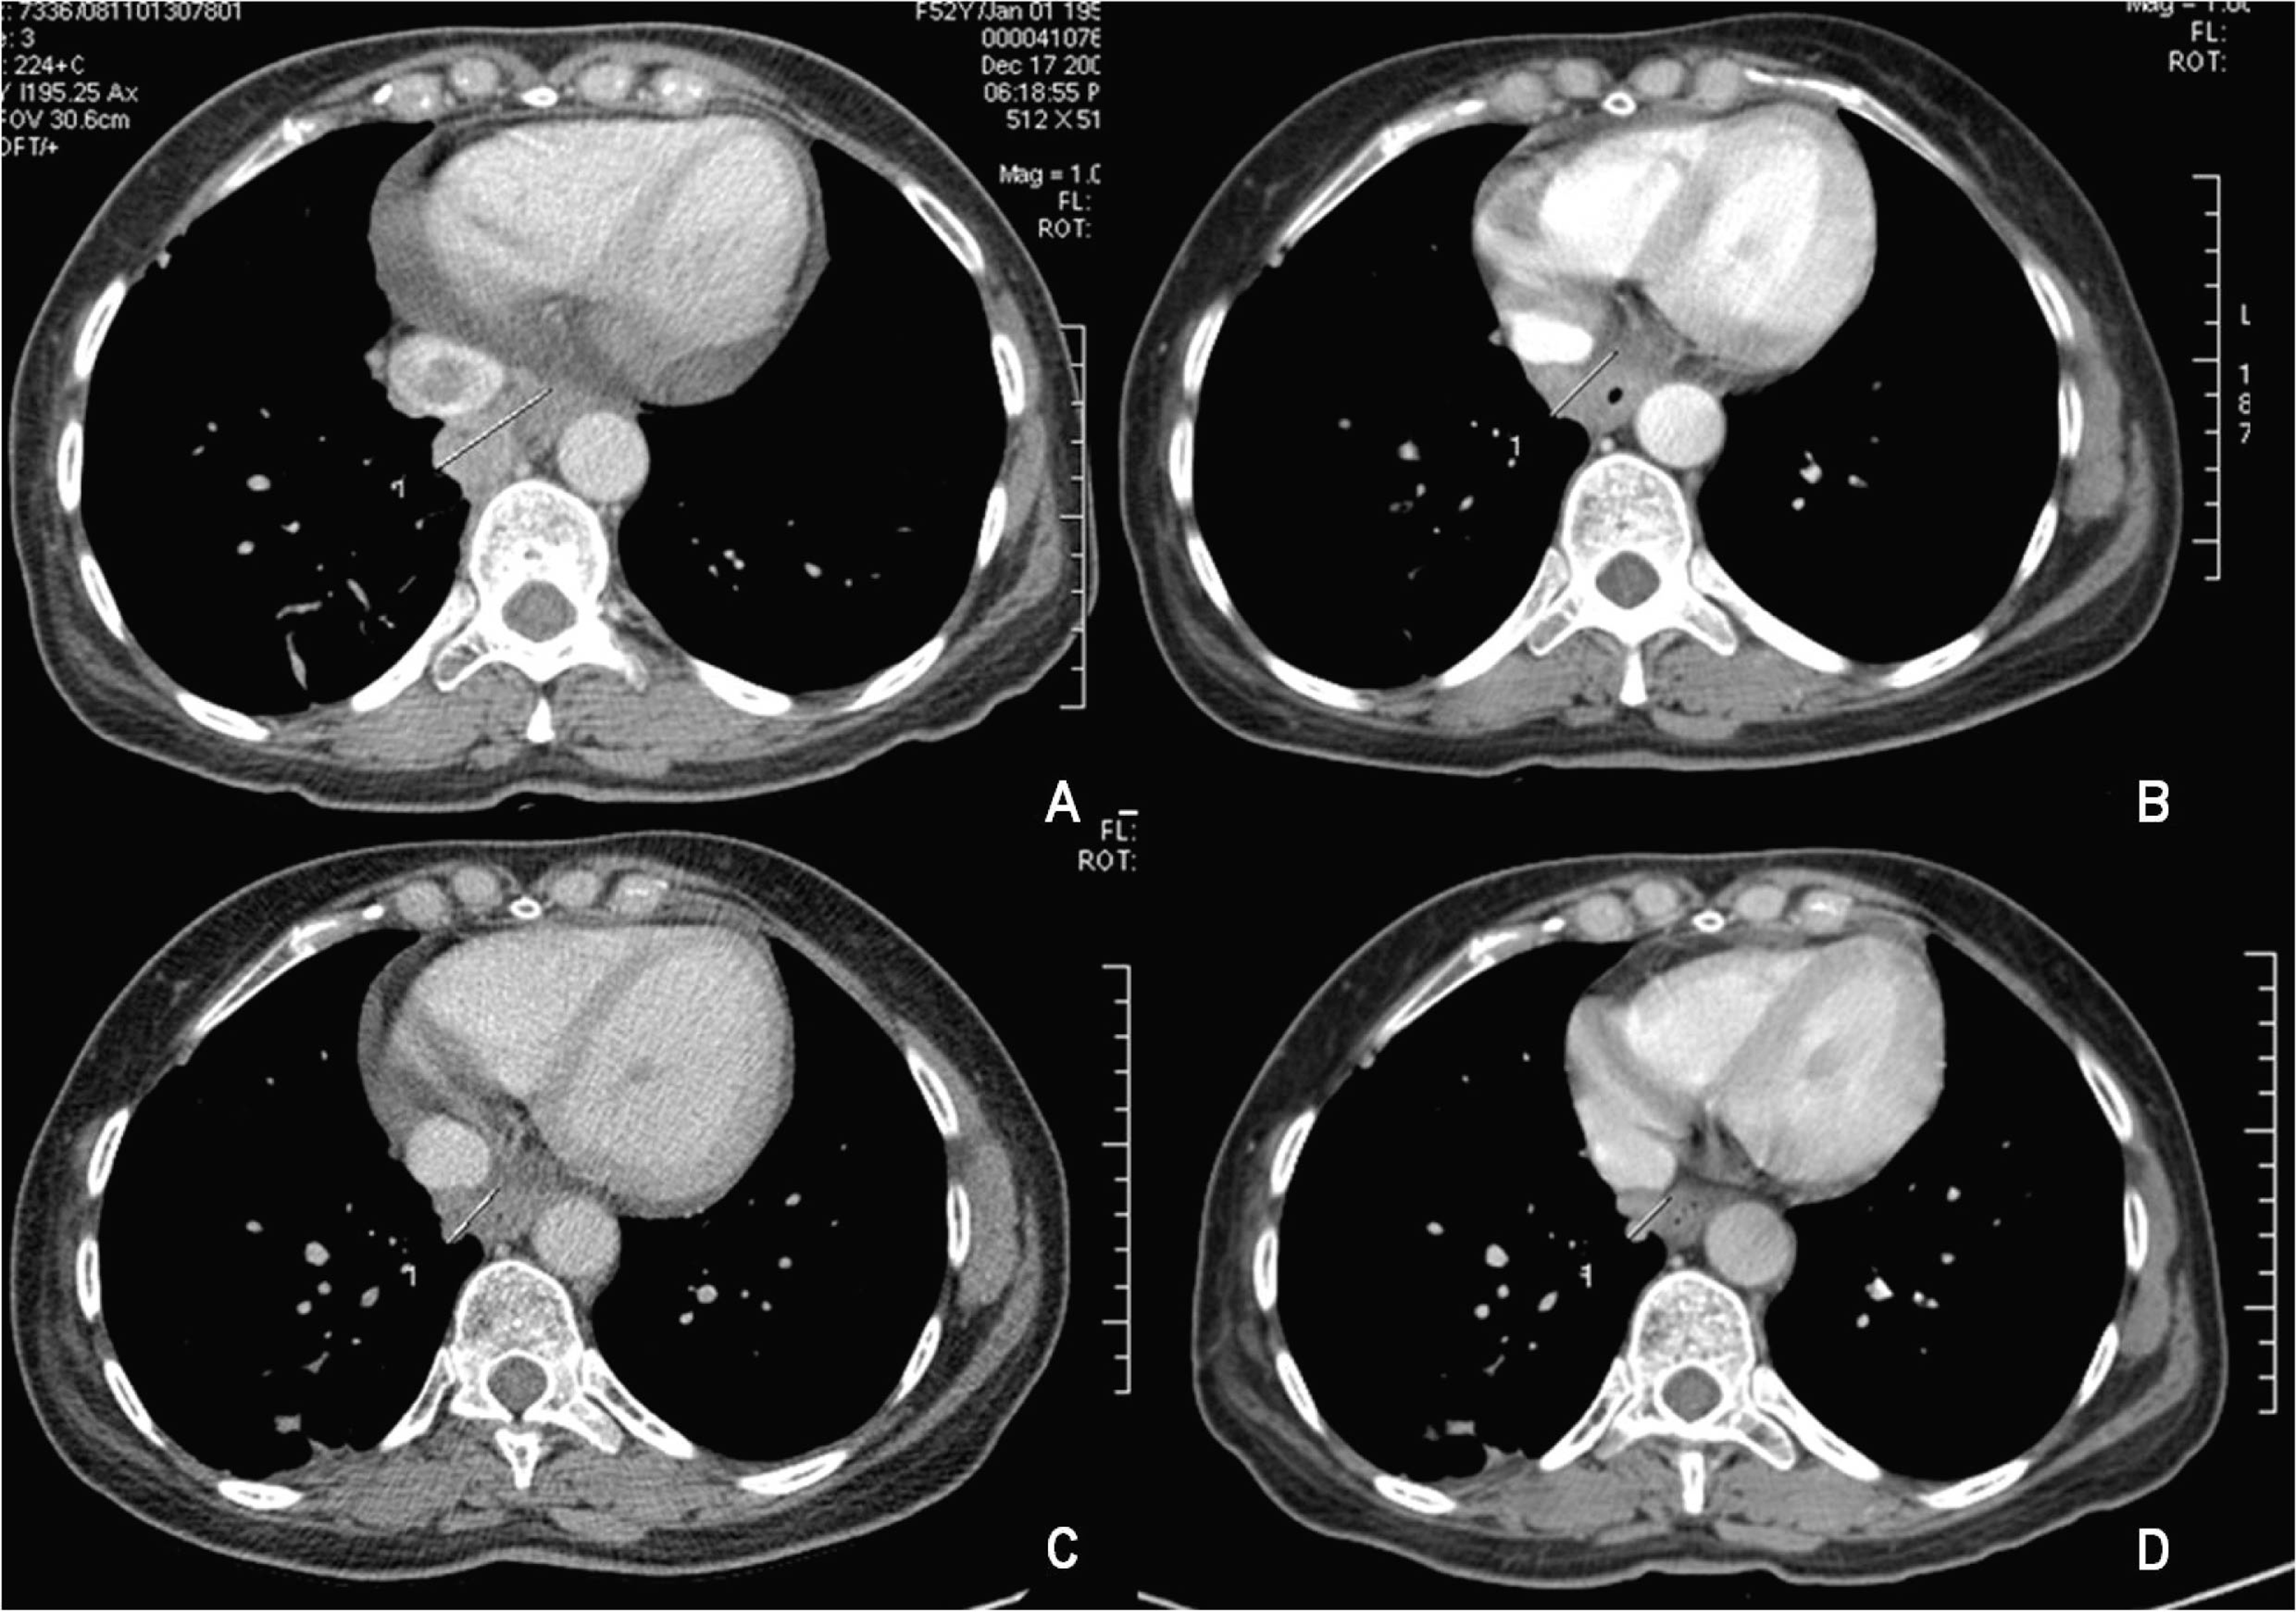

A rising AFP contrasted with the absence of demonstration of any tumor in repeatedly imaging techniques. In December 2008, AFP peaked at 365.4 µg/L. At that time, a dynamic CT identified an inferior mediastinal mass of 3.5 x 3.3 cm associated with a vena cava thrombus. Sorafenib (400 mg twice daily) was started in February 2009 (AFP of 464 µg/L, DNA VHB of 7310 UI/mL, normal transaminases) resulting in a decline of AFP values and a reduction of more than 50% of the metastatic mass (15 mm wide in March 2010) and of vena cava thrombus size (Fig. 2). Antiviral treatment with lamivudine 100 mg/day was started simultaneously resulting in an undetectable HBV DNA 3 months after. The patient is asymptomatic, reporting only transitory hair loss during treatment.

![]() Click for large image | Figure 2. Mass involution under sorafenib treatment: (A) December 2008; (B) May 2009; (C) November 2009; (D) March 2010. |